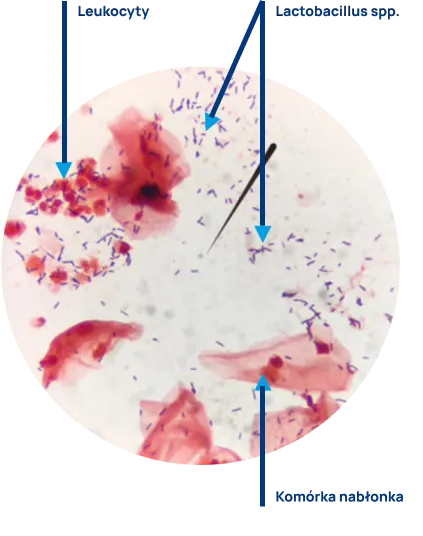

Badanie biocenozy pochwy (nazywane również oceną czystości pochwy lub mikrobiomu pochwy) polega na mikroskopowej ocenie wymazu z pochwy pod kątem określenia drobnoustrojów kolonizujących błonę śluzową. Wskazaniem do wykonania tego badania jest diagnostyka stanów zapalnych pochwy i dolnego odcinka układu moczowego oraz kontrola stanu mikrobiologicznego pochwy.

Wydzielina z pochwy pobierana jest wymazówką, przez lekarza lub położną, z tylnego sklepienia pochwy, po uprzednim założeniu wziernika. Z pobranego materiału wykonywany jest rozmaz na szkiełku, który po przekazywaniu do laboratorium zostaje wybarwiony i oceniony mikroskopowo.

Ocena preparatu mikroskopowego obejmuje opis liczebności pałeczek kwasu mlekowego, pozostałych bakterii, grzybów, nabłonków i leukocytów. Prawidłowy wynik badania (liczne pałeczki Lactobacillus spp., brak lub skąpa liczba pozostałych bakterii, brak leukocytów, brak grzybów) wskazuje na równowagę drobnoustrojów w pochwie. Nieprawidłowy wynik badania (zaburzenie biocenozy pochwy) nasuwa podejrzenie zakażenia i jest wskazaniem do dalszej diagnostyki i podjęcia leczenia.

Fot. Aleksandra Johaniuk Pracownia Mikrobiologii ALAB laboratoria Sp. z o. o. Szczecin